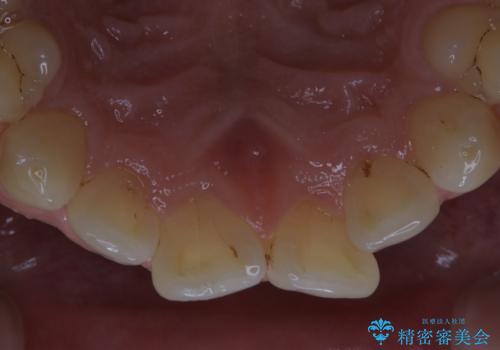

細かいステインをPMTCでOFF

- 歯ブラシをしてもとれないステインが気になるとのことで来院されました。PMTC60分コースを行いました。

PMTCは、歯に付着した汚れを除去していくため、着色が気になる場合にも行うことができます。ご自身でのセルフケアだけで着色を落とそうとすると、逆に歯を傷つけてしまったり、精密に汚れを除去できないこともあります。また、日常生活で着色しやすい飲食物を避けたりすることはストレスに感じてしまったり、あまり現実的ではありません。

毎日丁寧に歯磨きをしていても、日常生活での飲食物などにより着色してしまうことはあります。PMTCでは、歯の表面の凸凹にミネラルを補給して、ツルツルの表面に仕上げます